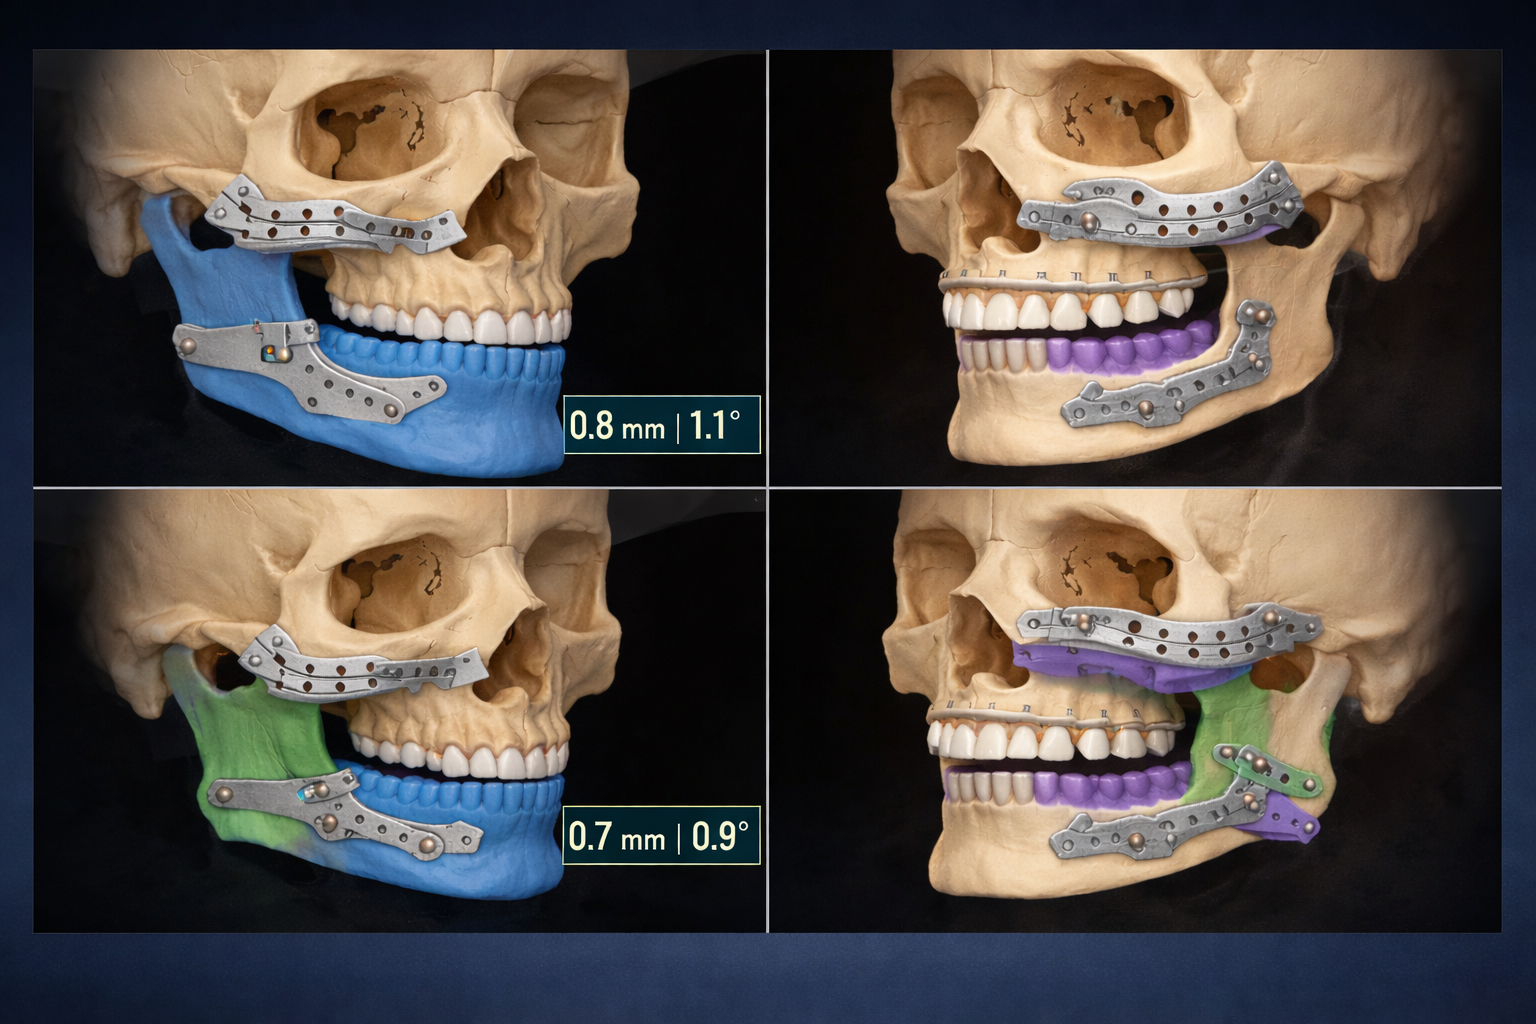

Does Surgical Sequencing Still Matter in Fully Digital Bimaxillary Orthognathic Surgery?

A Retrospective Accuracy Study of 46 PSI‑Guided Cases

Digital precision meets clinical decision-making: This study shows that in PSI-guided bimaxillary orthognathic surgery, both mandible-first and maxilla-first sequences achieve equally high accuracy. Virtual surgical planning ensures predictable, patient-specific outcomes, highlighting that technology can transcend traditional sequencing debates.